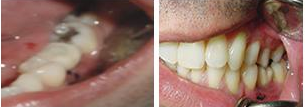

Paciente número 0283, de 46 anos de idade. Chegou à clínica com um abscesso

no dente 12. Queixava de muita dor e desconforto.

No exame clínico pode-se ver que havia grande mobilidade da coroa, estava

praticamente solta.

O exame radiográfico mostrou uma pequena linha de fratura. Foi indicada a extração do dente.

A paciente ficou muito abalada em ficar sem o dente, por questões estéticas. Foi proposta uma PPR ou mesmo um dente ser colado no lugar, o que deixou a paciente insegura.

Propusemos a colocação de um implante lançado pela Conexão, o Conect, que permite a colocação imediata de uma coroa estética no implante colocado, não sendo necessário para isso a espera de 6 meses para a osseointegração.

Prontamente a paciente achou excelente idéia, indicando a colocação de implante Conect.

Figura n°1. Caso clínico: Paciente de 46 anos de idade, já portadora de 4 implantes, colocados há 6 anos, compareceu ao consultório após a perda da coroa do dente 12 com fratura da raiz.

Figura n°2. A análise radiográfica, mostrou uma raiz com muito pouca implantação, reação apical e ao exame clínico uma provável linha de fratura, transversal, alterando o ligamento periodontal no terço médio da raiz. Assim a raiz foi condenada, e indicado à paciente um implante imediato. Na radiografia pode-se observar outras alterações nos ápices dos dentes 13 e 14.

Figura n°3. Esta é a fotografia antes da cirurgia para implante. A imagem não ficou boa, mas pode-se notar com atenção uma linha de fratura iniciando na região vestibular com direção à distal.